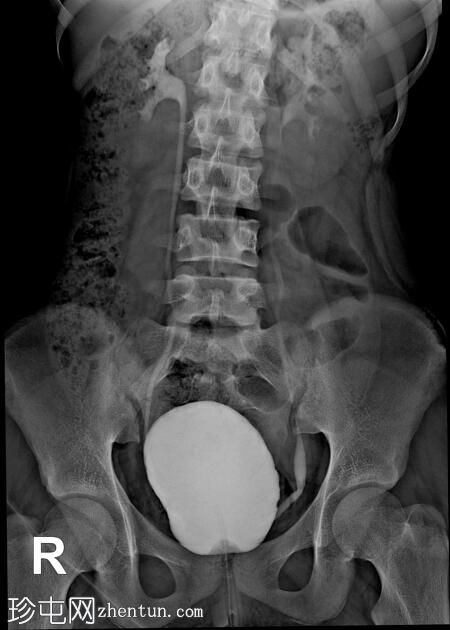

年龄:12岁

性别:女

透视检查

正位

排尿性膀胱尿道造影显示尿液反流至

肾脏

,伴有输尿管和肾盂肾盏系统轻度扩张。

还观察到排尿后残余尿。

本病例描述了一例有复发性尿路感染病史的儿童,其双侧3级膀胱输尿管反流。